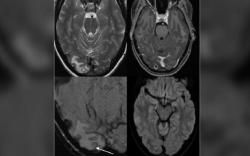

Infeksi Larva Cacing Pita